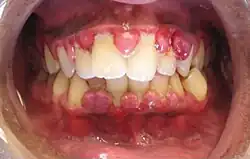

![]() | |

| A severe case of gingivitis | |